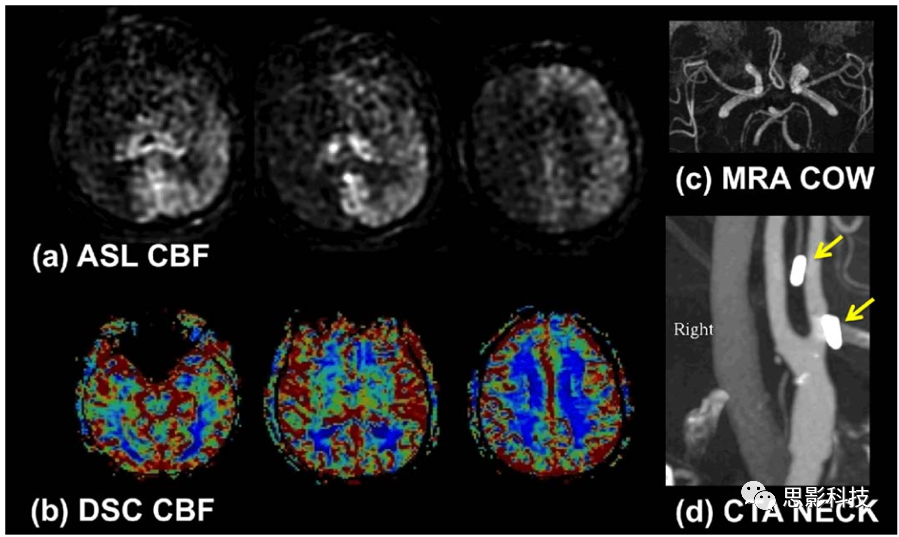

Figure 4由于标注质量较差导致的CBF计算结果与DSC的对比

1、对PCASL扫描,可查看低标注效率的范围。首先,需要确定哪些动脉被标记。通常来说我们需要标记的有颈内动脉、外动脉和椎动脉。在血管造影可用的情况下,可用于标记动脉的位置。检查血管的Willis 圈也可用于匹配血管区域和标记的动脉。当某条动脉的标记较低时,这条动脉的区域会显示较低的CBF值。当发现低CBF区域的,与血管的区域相吻合时,且无其他动脉代偿时,就有标注失败的可能,当然这样可能是低CBF以及ATT异常导致的。标注失败可能是由弯曲的血管或标记平面中的共振偏移引起的。前者可通过调整标注平面的位置来解决,在这种情况下,额外的血管造影会有所帮助。后者通常是由牙齿活动引起的,并且可能是由该患者在其他图像中牙齿周围的信号丢失所建议的。上面讨论了解决PCASL中与共振偏移相关的标记问题的方法。

4、检查血管内伪影。高强度斑点和蛇形区域通常代表血管内信号。观察时,建议验证PLD是否适合患者,因为低PLD会自然在较大的动脉中产生ASL信号。具有正确PLD的动脉内信号表明,标记的血液通过缓慢的流动或间接的循环途径而延迟了向组织的输送。静脉ASL信号提示存在动静脉分流。请注意,如果不使用血流损毁梯度,则在存在血管内伪影的情况下,需要用整个大脑或较大目标区域的CBF计算。